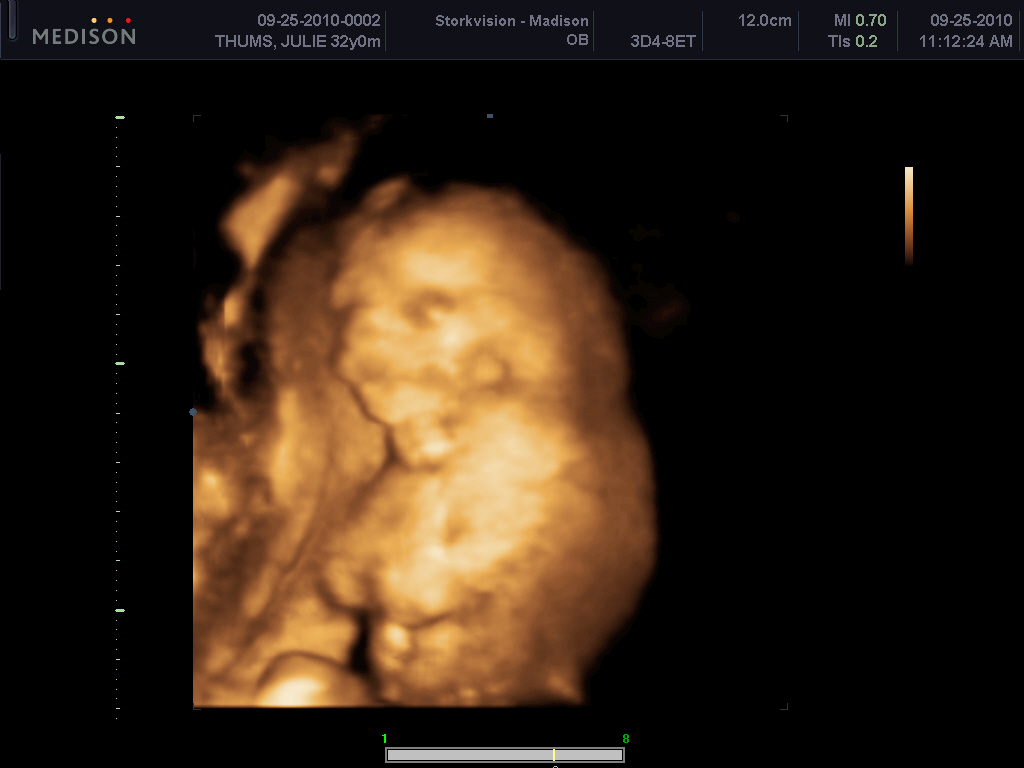

AND FOR WHAT YOU ARE ALL REALLY HERE FOR......

yep.... 100% boy :)